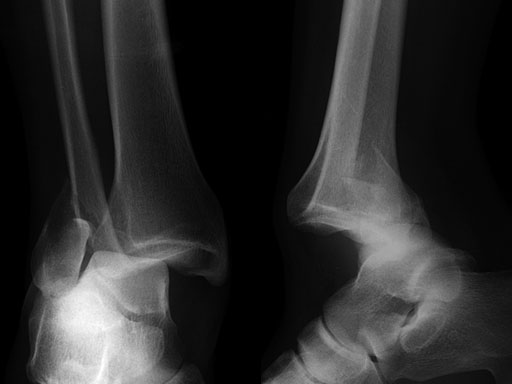

A 56-year-old man slipped and fell, sustaining a fracture dislocation of the ankle. His fibula was stabilized with a posterolateral plate. The construct included several nonlocking screws in the diaphysis, and multiple 2.7 mm locking screws in the distal fibula. As with most Weber B fracture patterns, a lag screw was possible from posterior to anterior through the plate. Finally, intraoperatively the patient was found to have a syndesmotic injury, and after reduction, a syndesmotic screw was placed through the plate.